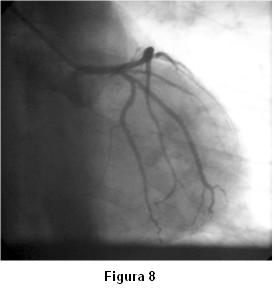

Antes de la finalización del estudio de la coronaria izquierda reitera espasmo (figura 6) que mejora sin necesidad de administración de vasodilatadores (figuras 7 y 8).